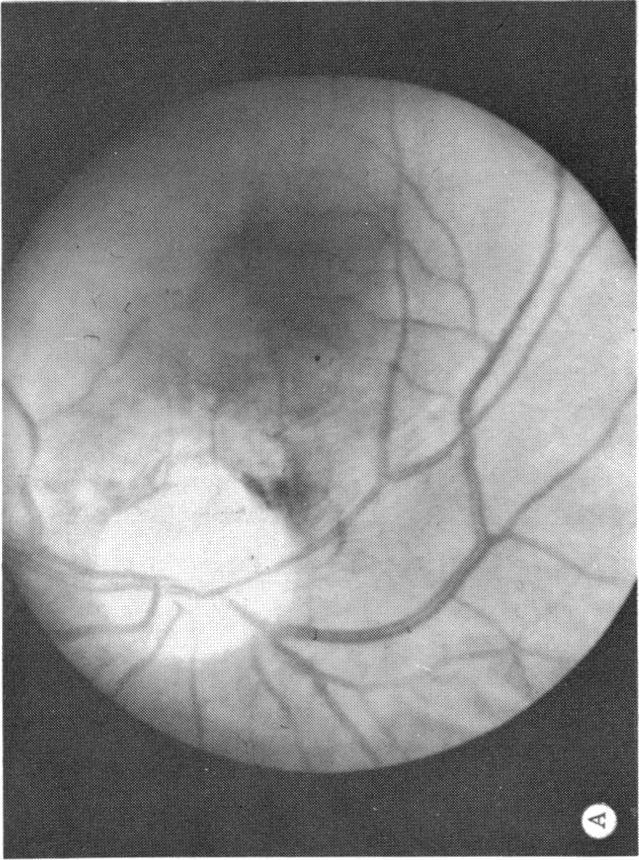

Six cases of congenital pit of the optic nervehead associated with posterior serous retinal detachment are presented. All were treated by photocoagulation along the disc margin in the area of retinal detachment. In five cases reattachment of the retina occurred, after the clinical development of a film chorioretinal adhesion at the disc margin, and appeared to be secondary to the treatment. The sixth case (Case 4), although treated, appeared to represent a spontaneous reattachment. This disorder, which frequently results in permanent decrease of central vision, affected the better, or only, eye in two of the six cases herein reported. Fluid, probably from the vitreous cavity, appears to gain access to the subretinal space via the pit. Reattachment in treated cases occurred only if an effective chorioretinal adhesion was created over the entire area of the fistulous detachment at the disc margin. Field defects after treatment appear to be secondary to either the optic pit itself or the longstanding retinal detachment, oftern accompanied by pigmentary degeneration and cystic macular degeneration, rather than juxtapapillary photocoagulation treatment.

本文报告6例先天性视神经乳头凹合并浆液性视网膜脱离。所有病例均采用视网膜脱离区域沿视盘边缘光凝治疗。5例视网膜脱离在视盘边缘形成脉络膜视网膜粘连后复位,似乎是治疗的继发结果。第6例(病例4)虽经治疗,但似乎是自发复位。这种疾病常导致中心视力永久性下降,在本文报告的6例中有2例影响了较好或仅有的一只眼。液体可能来自玻璃体腔,似乎通过视神经乳头凹进入视网膜下间隙。治疗病例中,只有在视盘边缘瘘管性脱离的整个区域形成有效的脉络膜视网膜粘连时,视网膜才会复位。治疗后的视野缺损似乎继发于视神经乳头凹本身或长期视网膜脱离,常伴有色素性变性和黄斑囊样变性,而非视盘旁光凝治疗。